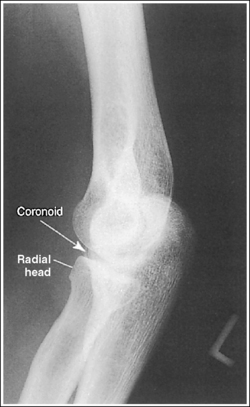

The elbow is positioned in an AP projection. The medial and lateral humeral epicondyles are demonstrated in profile at the extreme medial and lateral edges of the distal humerus, and the radial head is superimposed over the lateral aspect of the proximal ulna by approximately 0.25 inch (0.6 cm). The coronoid process is demonstrated on end.

• Detecting elbow rotation. Rotation of the elbow is a result of poor humeral epicondyle positioning and can be identified on an image when (1) the epicondyles are not visualized in profile, (2) the radial head is demonstrated with more or less than 0.25 inch (0.6 cm) superimposition of the ulna, and (3) the coronoid process is seen in profile. The smaller, lateral humeral epicondyle is more sensitive to rotation, moving out of profile with only a slight degree of elbow rotation. If the epicondyles are not demonstrated in profile, evaluate the degree of radial head superimposition of the ulna to determine how to reposition for an AP projection. If more than 0.25 inch (0.6 cm) of radial head is superimposed over the ulna, the elbow has been internally rotated (see Image 74). If less than 0.25 inch (0.6 cm) of the radial head is superimposed over the ulna, the elbow has been externally rotated (see Images 75 and 76).

The radial tuberosity is demonstrated in profile medially, and the radius and ulna are parallel.

The capitulum-radius joint is open, the radial head articulating surface is not demonstrated, the olecranon process is situated within the olecranon fossa, and the coronoid process is demonstrated on end.